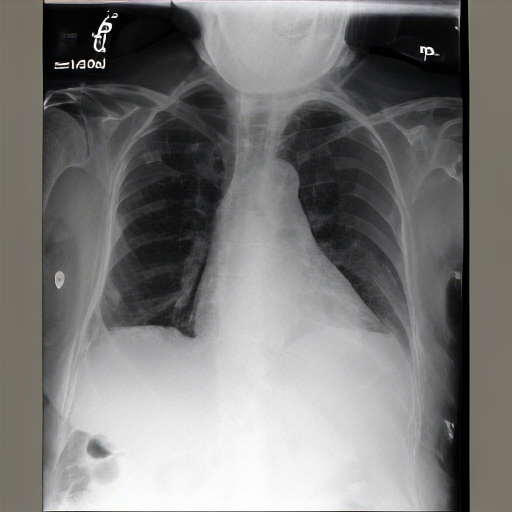

PA and lateral chest radiographs demonstrate hyperinflated lungs, suggestive of COPD. Otherwise, there is no focal consolidation, pleural effusion, or pneumothorax. The cardiomediastinal and hilar contours are normal. No acute osseous abnormalities are detected. No acute cardiopulmonary abnormality is present. Postsurgical changes are noted in the upper abdomen.

FINDINGS: The lungs are hyperinflated but without focal consolidation. No pleural effusion or pneumothorax is seen. The cardiac and mediastinal silhouettes are unremarkable. No pulmonary edema is seen. Bilateral hila are unremarkable. IMPRESSION: Lungs remain hyperinflated, suggesting possible COPD. No focal consolidation is seen.